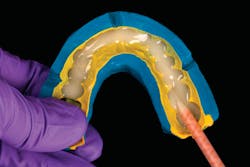

A patient presented with multiple deficient restorations, discolored teeth, and attrition (figures 1–4). The patient’s treatment plan was a full-mouth rehabilitation with a combination of veneers, crowns, and onlays.